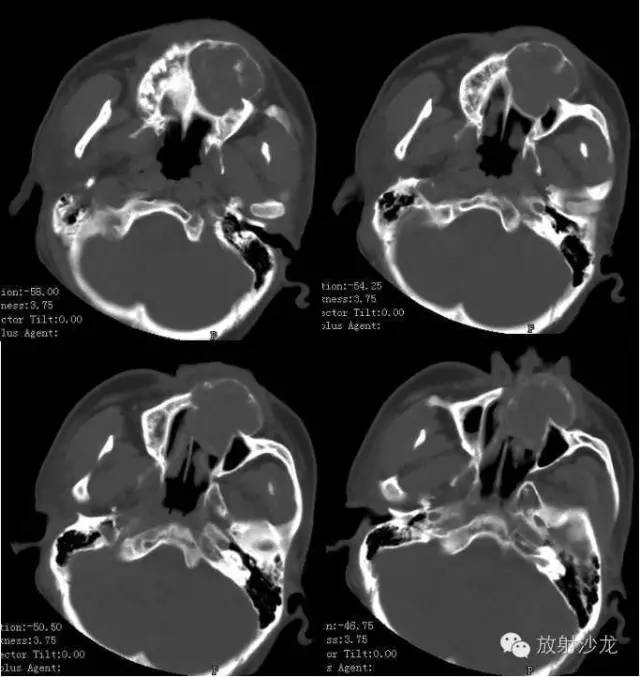

【术前CT扫描图像】

术前CT诊断:左侧下颌骨不规则膨胀性骨质破坏区,内可见软组织及残存骨嵴,病灶累及牙槽骨及筛窦壁,考虑造釉细胞瘤可能性大。

【影像学表现】

X线平片及CT上表现溶骨性骨质破坏,其中有骨性分隔,伴有轻度膨胀,可发生在干骺端和骨干,也可伸展到骨骺和软骨下骨质,病灶无骨膜反应;